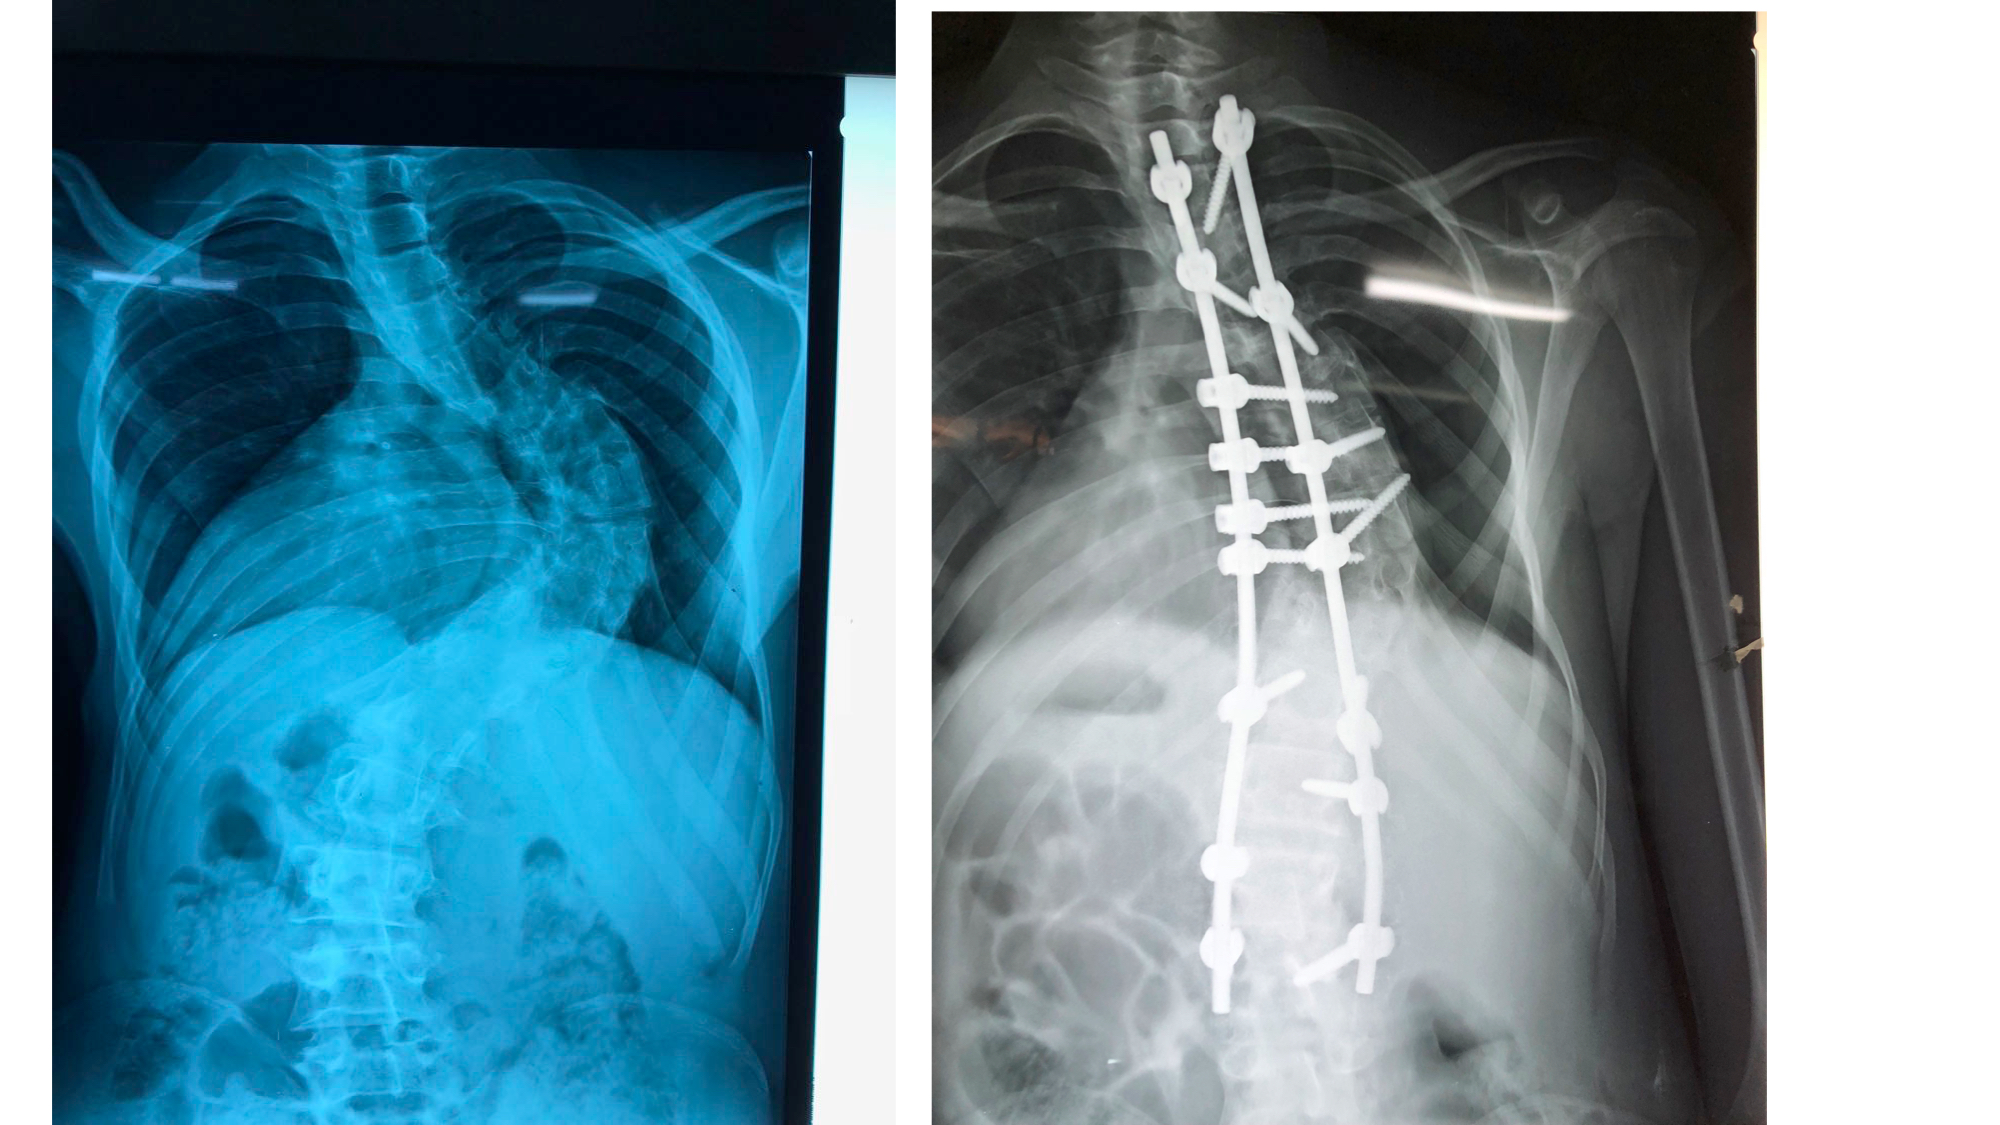

I was also able to meet the first two spine surgery fellows at AaBET. They are both neurosurgeons. The plan after next year is to alternate orthopedic with neurosurgery spine fellows. In addition to their teaching at AaBET, they are mentored by Dr Fasil Mesfin of Univeristy of Missouri, with whom they have weekly cases conferences. They were excited to show me two massive spine tumors they just operated on, one a giant, dumbbell shaped neurofibroma of the lower thoracic spine with bone involvement and preoperative paraparesis; the other a huge aneurysmal bone cyst of posterior lumbar element. Both needed pedicle screw instrumentation and big exposures. I am not a spine surgeon but the operative photos and postop xrays were very impressive.